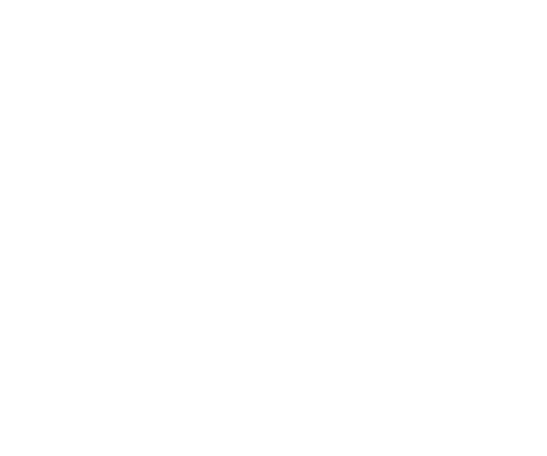

Le système XCP est classé par couleurs en fonction de l’emplacement et du traitement à effectuer :

- Le XCP Bleu est conçu pour la prise de radiographies périapicales dans le secteur Anterieur

- El XCP Jaune est conçu pour la prise de radiographies périapicales dans le secteur Posterieur